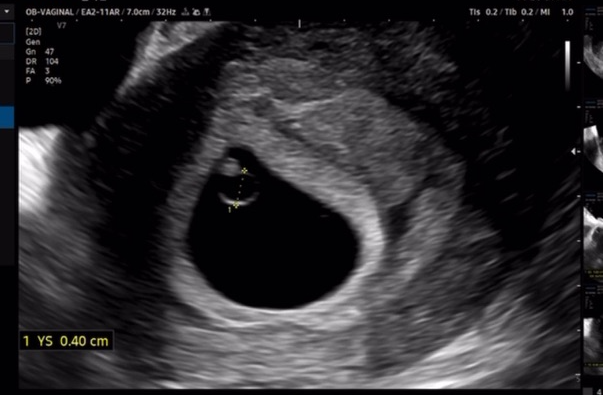

그리고 왕배집을 보여주셨다.

왕배는 현재 5주 5일 차로 0.5cm였다.

0.5cm 되는... 아직 세포라고 생각했는데 심장이 뛰다니.